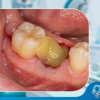

Bệnh nha chu thường bắt đầu từ viêm lợi, một tình trạng viêm nhiễm nhẹ ở nướu. Nếu viêm lợi không được điều trị, nó sẽ tiến triển thành viêm nha chu, phá hủy các mô nâng đỡ răng, tạo thành các túi nha chu.

Nha chu là bệnh lý nghiêm trọng ảnh hưởng đến các mô nâng đỡ răng, bao gồm nướu, xương ổ răng và dây chằng nha chu. Nếu không được điều trị kịp thời, nha chu có thể dẫn đến mất răng. Viện Nha Khoa Quốc Tế 4.0 cung cấp dịch vụ điều trị nha chu toàn diện, giúp bạn bảo vệ răng miệng và duy trì nụ cười khỏe mạnh.

Việc phát hiện và điều trị nha chu sớm là rất quan trọng để ngăn ngừa mất răng và các biến chứng khác. Các triệu chứng của bệnh nha chu bao gồm:

- Nướu đỏ, sưng, dễ chảy máu

- Hôi miệng kéo dài

- Tụt nướu, răng trông dài hơn

- Răng lung lay

- Đau khi nhai

- Thay đổi khớp cắn